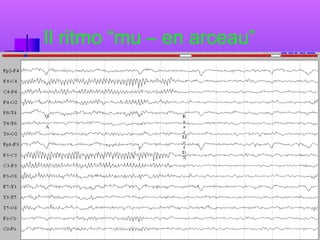

Oberman e Ramachandran (2005)

Evidenza dell’assenza della reazione di

Il ritmo “mu – en arceau”